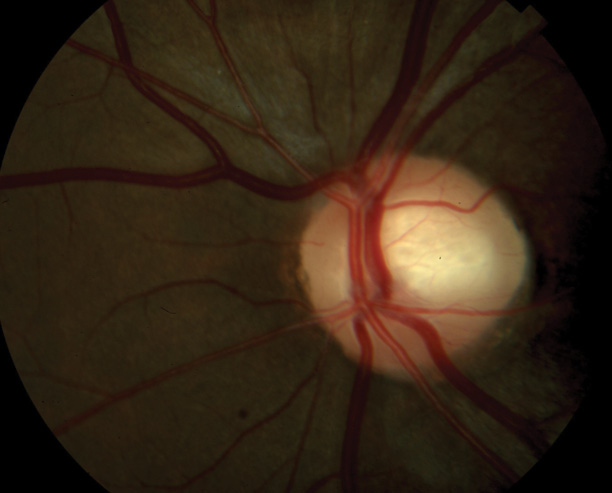

Figure 1. Optic nerve of a 24-year-old woman observed for low-tension glaucoma.

The glaucoma examination is more challenging than a routine eye examination. The former requires a detailed evaluation of both the posterior and anterior segments, including the angle. I look for clues to secondary glaucomas that someone else may have missed or for evidence of retinal or neurologic pathology that is mimicking glaucoma. I am sure all of my colleagues have examples of patients who were monitored elsewhere for low-tension glaucoma who actually had an intracranial tumor (Figures 1 and 2).